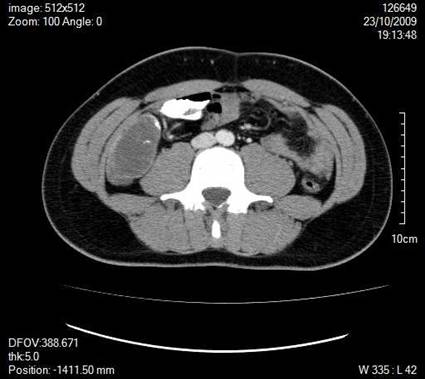

A 30-year old man presented with symptoms and signs of acute appendicitis. Abdominal imaging via ultrasound and computed tomography detected a mass in the right iliac fossa. Exploratory laparotomy revealed an appendiceal mass and gelatinous peritoneal fluid, while histopathology confirmed the diagnosis of pseudomyxoma peritonei arising from a mucocele of the appendix and attributed to an appendiceal cystadenocarcinoma. The clinical and imaging findings of this rare case are herein presented.